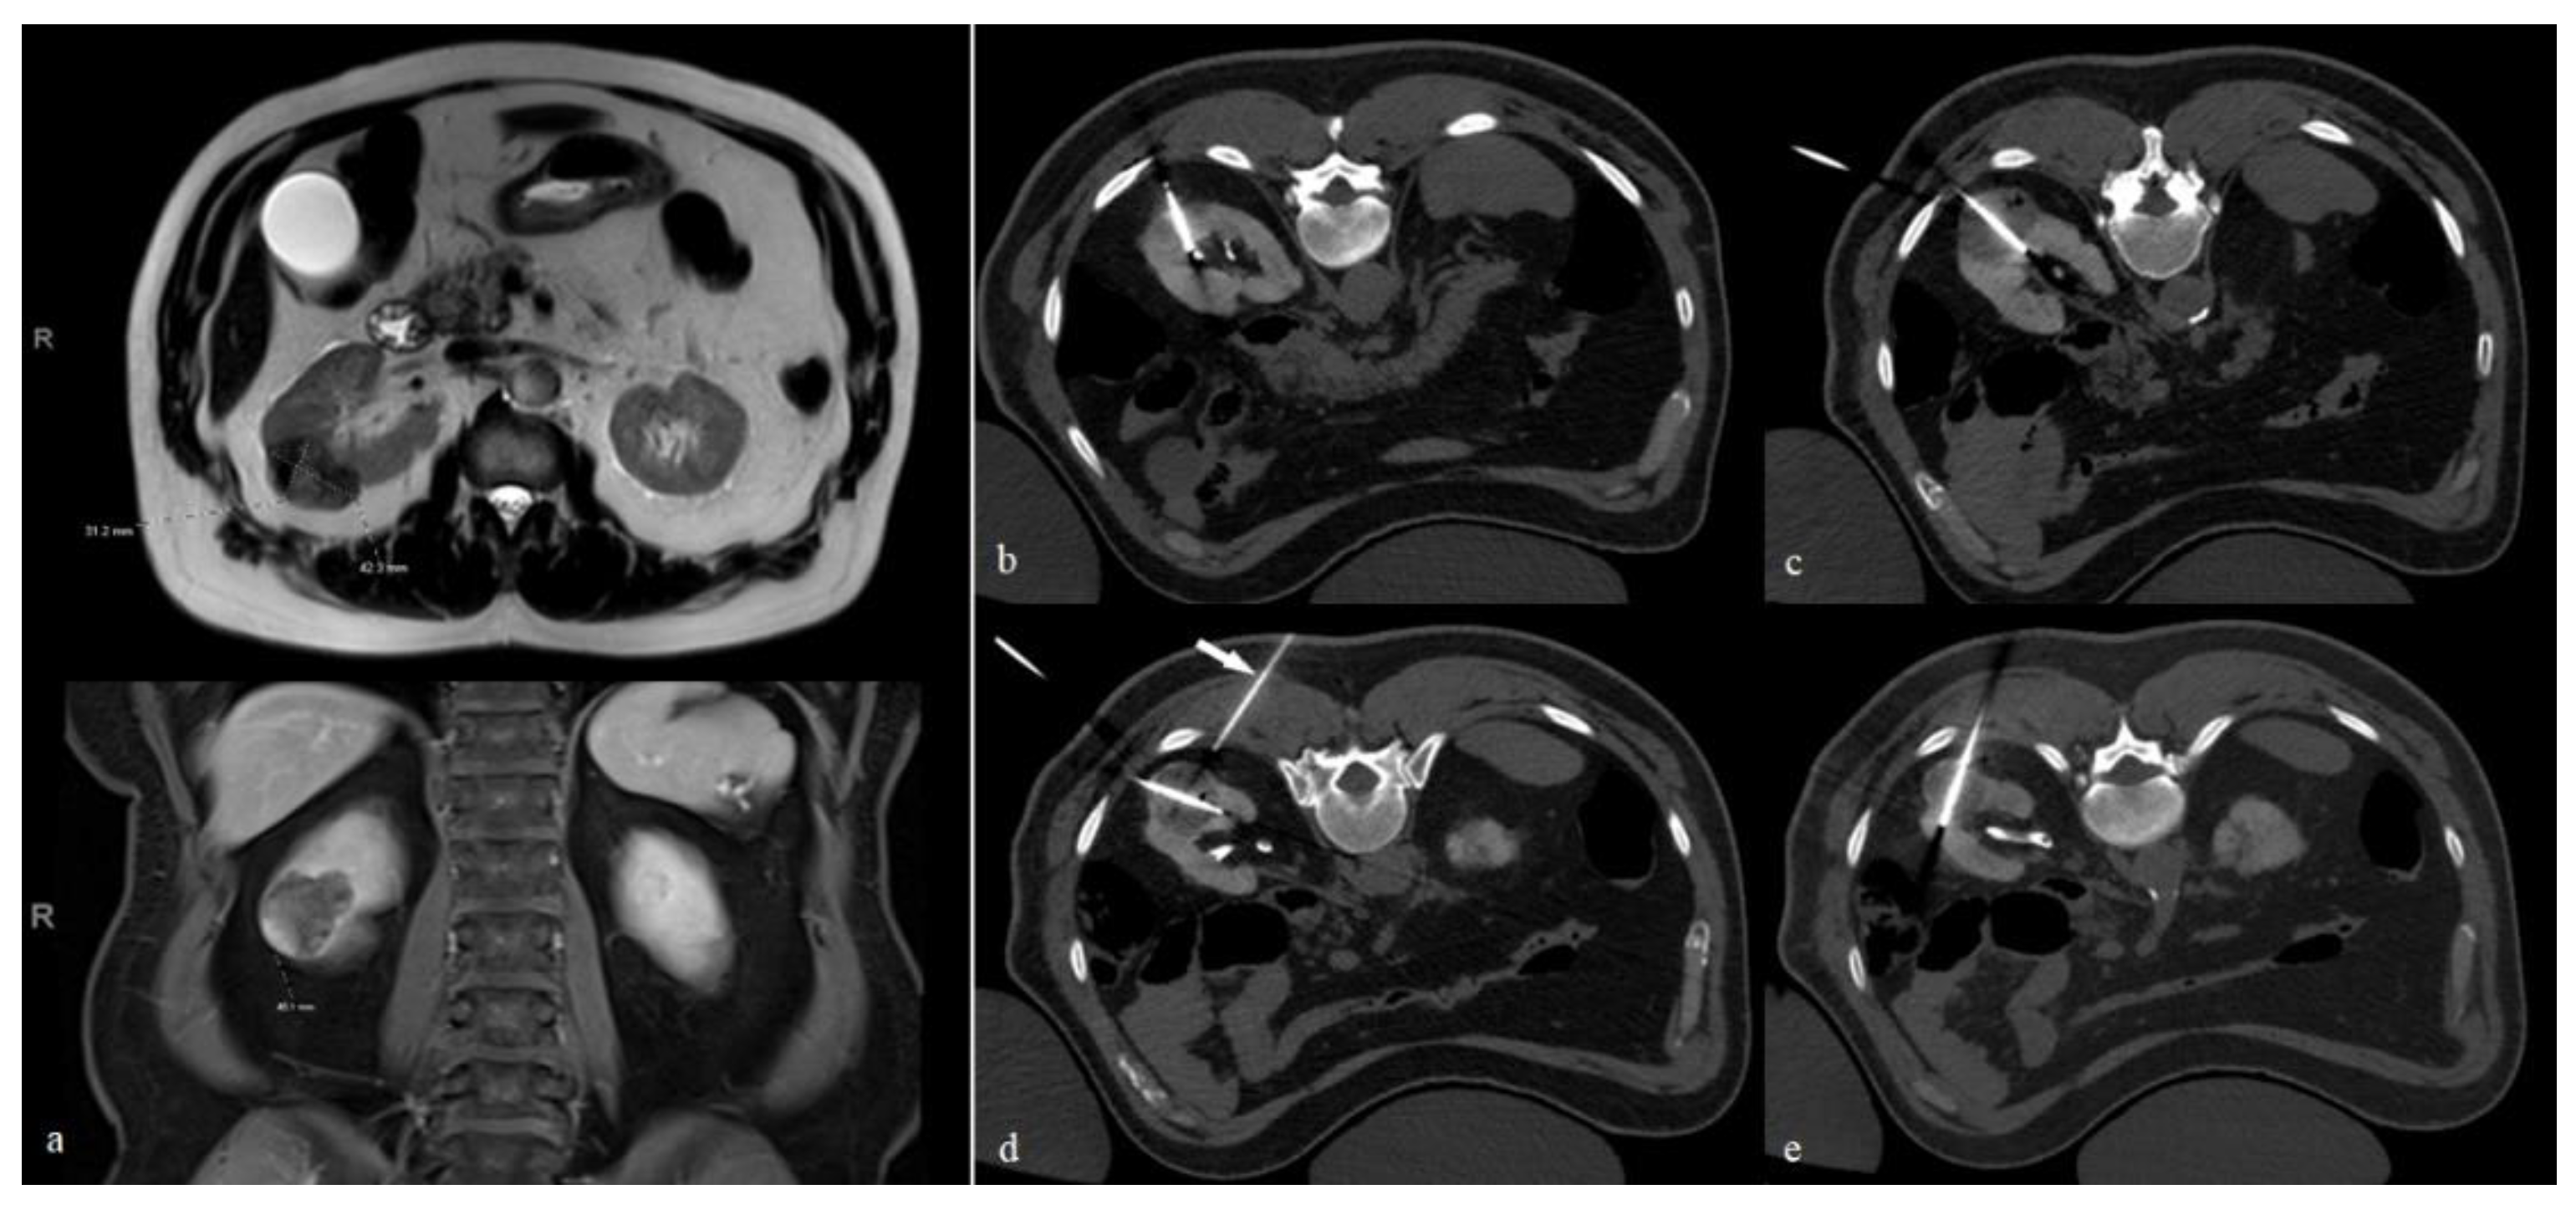

Figure 1. Cryoablation of a right renal RCC. (a) MRI scan shows a right renal partly exophytic mass, measuring 4.2 × 3.1 × 4.5 cm along the axial and craniocaudal dimensions, respectively. (be) Four cryoablation probes are carefully aligned along the longitudinal axis of the mass from cranial to caudal. In our experience, the orientation of the probe shown in figure (e) is critical as it allows the ice ball to ablate the most central part of the mass, which is a common site for recurrence. The arrow in (d) points to a 21 G needle used for CO2 dissection, as shown in Figure 2.

Generally, better outcomes can be achieved by placing cryoprobes parallel to the longitudinal axis of the lesion. This is particularly important when using cryoprobes with larger ablation zones, such as the IceFORCE ® 2.1 CX (Galil Medical Inc., MN, USA), which usually produces an ice ball that is greater in length than width. However, the non-uniform shape of these tumors can make probe placement along the longitudinal axis technically challenging. In our experience, the most challenging portions to ablate are the central and medial aspects of the tumor. These are also frequent sites of recurrence [9]. In this case, we recommend placing at least one probe along the longitudinal access of the lesion in the craniocaudal center and toward the medial aspect of the tumor (Figure 1).

Multiple cryoprobes, with 3–5 probes on average, are usually needed to treat large RCCs. To allow for the appropriate coalescence of the separate ice balls, we recommend a spacing of 1.5–2 cm between the probes. In our practice, we typically start by targeting the cranial and then the caudal ends of the tumor. We then place at least one probe along the longitudinal axis at the central/medial aspect of the lesion. We then fill in the gaps between the three initial probes using 1–2 additional probes. An effort is made to avoid traversing the back musculature, if possible. Care is also taken to minimize crossing the normal renal parenchyma as much as possible, although exceptions can be made to ensure appropriate coverage of the target lesion. Careful planning is essential to avoid non-target freezing of intercostal nerves, the genitofemoral nerve, and adjacent bowel loops.

The second important factor to consider is efficacy. The ablation of large RCCs requires appropriate planning to ensure complete coverage of the tumor and minimize the chances of leaving residual viable tissue. For this reason, we prefer to perform cryoablation under a general anesthetic (GA). GA allows for appropriate breath-holding during the procedure. This is extremely useful for larger tumors, which necessitate multiple cryoprobes being positioned and spaced with precision. We always place our probes along the longitudinal axis of the lesion to allow for the inclusion of most of the tumor within the growing size of the ice ball.

As mentioned, an average of 3–5 probes are needed for the ablation of large RCCs. Using multiple probes with such tight spacing can be technically confusing. Thus, we recommend attempting to place the probes along different trajectories to easily identify the individual probes. Ideally, the ice balls formed by individual cryoprobes should coalesce into a uniformly large-sized ice ball that covers the whole volume of the tumor. However, tissue characteristics, including perfusion and necrosis, may interfere with this process. As such, it is important to check on the growth of the ice ball with an intra-procedural CT scan to ensure adequate coverage of the target mass and confirm that the ablation does not extend beyond the intended ablation volume. In our experience, the size of the ice ball formed by the second freezing cycle is slightly larger than in the first cycle. Judging the adequacy of ablation should thus be performed at the end of the second freezing cycle.